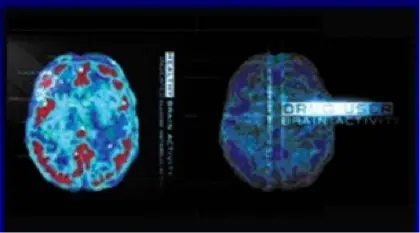

Addiction Compared to Other Chronic Diseases

- Glucose uptake in the brain and heart - both addiction and heart disease produce observable changes in organ function.

- The healthy organ shows greater activity (reds and yellows) than the diseased organ.

- In drug addiction, the frontal cortex, which is a part of the brain associated with judgment and decision-making, is significantly affected.

- Like heart disease, drug addiction can be prevented and treated successfully.

- If left untreated, however, its effects can last a lifetime.